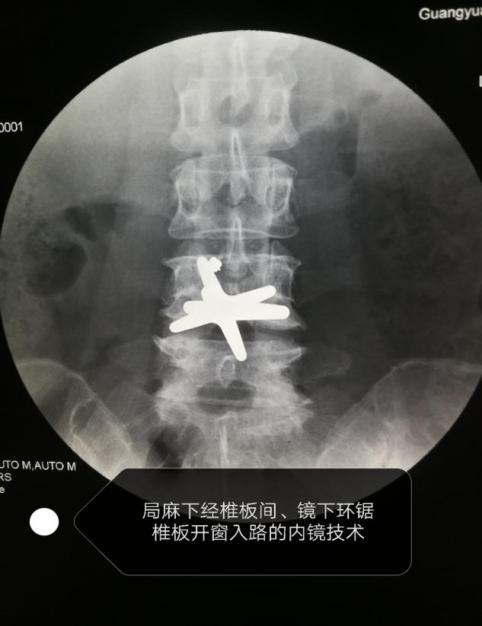

在介入放射科手术室,杨主任团队应用疼痛科关键技术——脊柱内镜技术,在局部麻醉下通过椎板开窗入路,脊柱内内镜下腰椎间盘髓核摘除术、椎间孔狭窄镜下椎间孔成型术、镜下脊神经后支松解术,成功摘除脱出游离腰椎间盘髓核。手术效果立竿见影,朱女士疼痛症状明显缓解,术后即可下床行走,5天后痊愈出院。

手术过程图示

杨四海介绍,该病例较特殊,在诊断及治疗上都有一定难度,遇到影像诊断与症状体征不相符合时,要进一步查找原因。腰椎间盘突出症、髓核沿椎管向上游离脱出较少见,微创手术难度较大。我们可以通过病灶靶点上下脊神经走行区,采用局部麻醉,内镜下可视环锯及椎板咬骨钳行椎板开窗入路,变换通道位置,摘除脱出游离髓核,解除患者腰腿痛、腰椎间盘突出症、盘源性腰痛等。